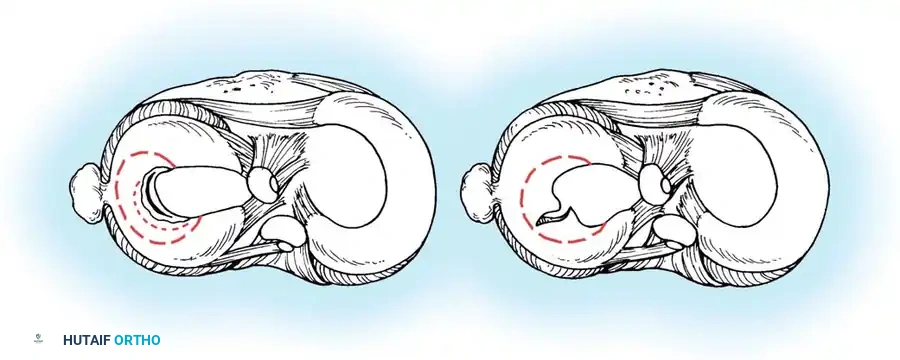

Intact hoop tension keeps the meniscus securely positioned between the articular surfaces during axial loading.

When a single radial cut or a complete root tear occurs, hoop tension is catastrophically lost. The meniscus extrudes, and its load-bearing capacity is effectively reduced to zero—biomechanically equivalent to a total meniscectomy.

Loss of hoop tension due to a radial tear or root avulsion allows the meniscus to extrude, eliminating its protective load-sharing function.